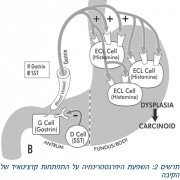

| 13:05, 14 במרץ 2016 | Hypergastrinemia3.jpg (קובץ) |  |

227 קילו־בייטים | Motyk | 1 | |